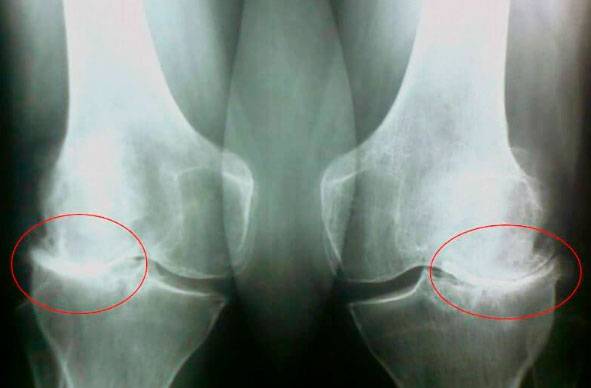

Погляньте на ці знімки, ви бачите, що на правому знімку суглобова щілина відсутня, кістки труться один об одного, викликаючи сильний біль. І цей процес дуже важко зупинити! Через пару років людина стане інвалідом і не зможе себе обслуговувати.

А. Конзюба : Насамперед, це травми та серйозні навантаження. Зайву вагу також надає сильний тиск на суглоби. Малорухливий спосіб життя, стреси, велика кількість солі і цукру в їжі все це розм'якшує хрящову тканину, зношує та стоншує її. Від кожного нового руху хрящ стирається і деформується, кістки починають тертися один об одного, викликаючи нестерпну біль.